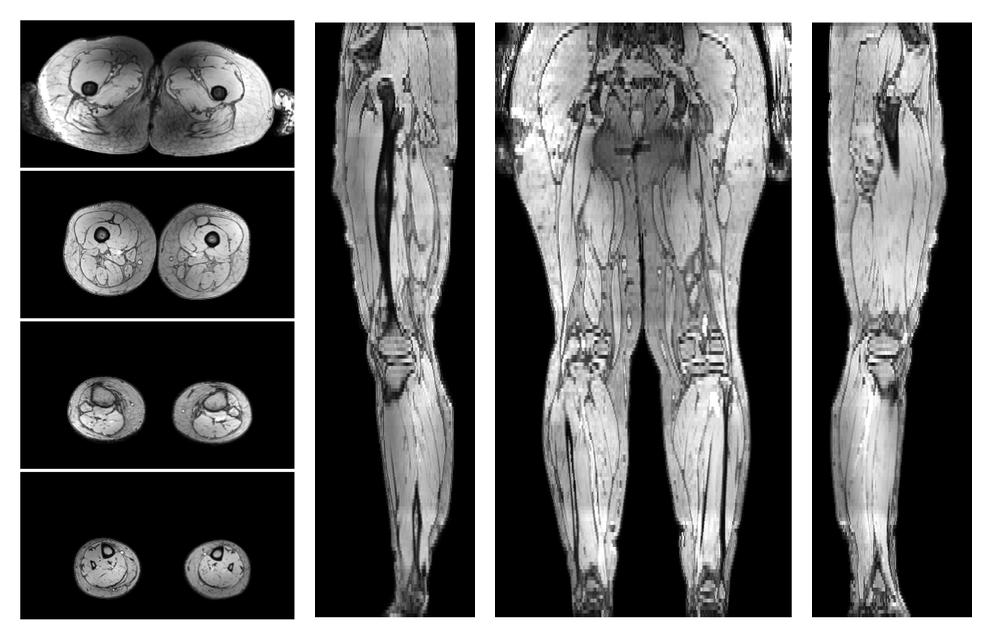

• Water only signal

The water part of the acquired multi-echo spin echo data.